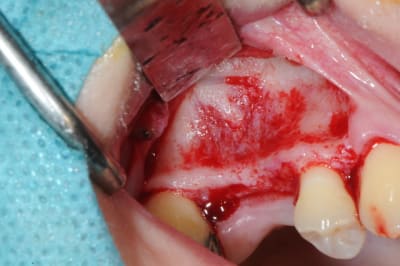

je sais pas si c'est un produit miracle, mais pour les sinus lift, c'est fantastique.

outre le fait de stabiliser un implant dans un sinus type SA4, pas de risque de voir partir le produit comme avec les granules de bioos et autres..

l'autre avantage est de ne pas avoir à mettre de membrane de recouvrement.

je suis donc hyper satisfait du résultat.

jugez plutôt...

l'application type du VitalOs, avec le bone splitting.